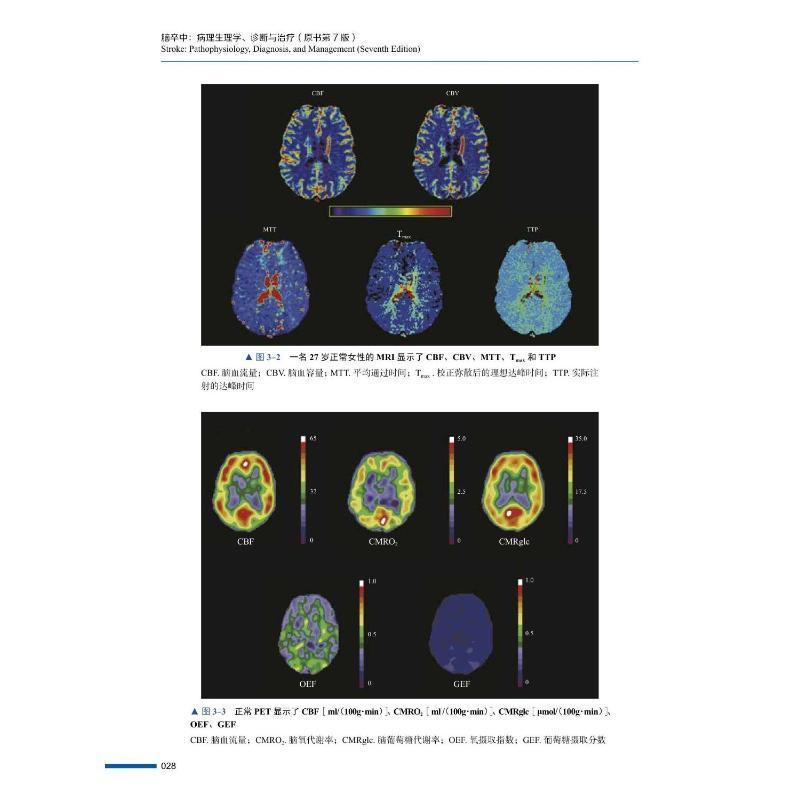

诊断与治疗 pathophysiology 原中国科学技术出版 脑卒中 社医药卫生书籍 mana9787523602546 病理生理学 and RT正版 diagnosis